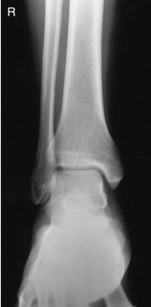

What is the correct evaluation criteria for an AP ankle projection?

distal one third of tibfib and lateral and medial malleoli, and talus and proximal half of metatarsals should be demonstrated